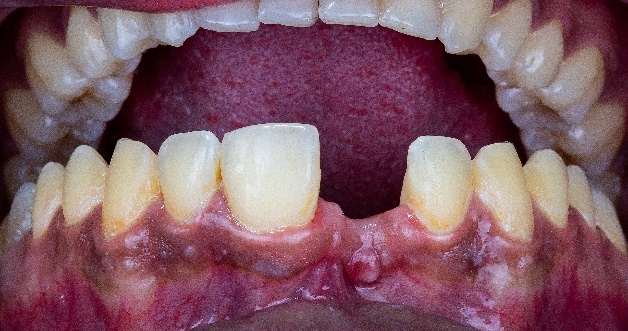

The scanbody is placed, and the Elite intraoral scanner is used to capture data for the design of the subsequent temporary crown. Since this is a single implant restoration, there’s no need to use IPG technology for determining the implant position (Fig 16, Fig 17).

The temporary crown try-in showed a good margin fit, evenly distributed occlusal contact points, and the morphology was confirmed by the patient. Later, the final zirconia crown was delivered to the patient, who expressed great satisfaction with the final result. (Fig 22,23,24,25)